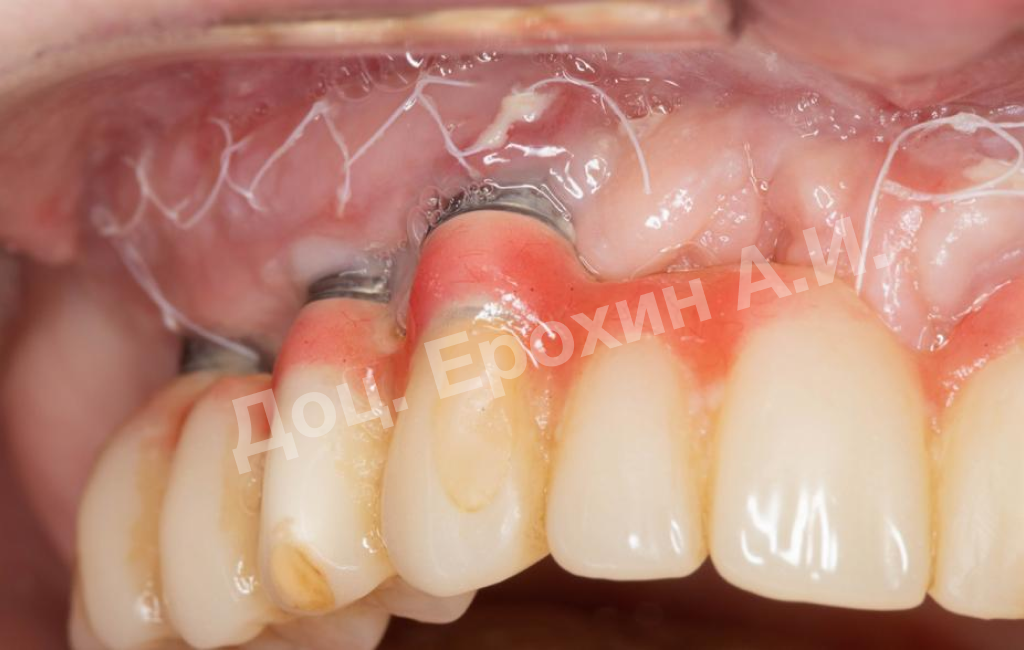

В результате, спустя 10 лет мы видим, что единственная часть десны в области имплантации, не затронутая рецессиями, — это зона, где была проведена трансплантация десневого фрагмента. С целью стабилизации имеющихся имплантатов на повторном приеме была проведена вестибулопластика по Кларку с фиксацией мягкотканных мукотомов, фрагментов эпителия с неба, зафиксированных швами.

В данном клиническом случае мы можем наблюдать эффект так называемого наползающего прикрепления (creeping attachment), когда десна после удаления момента натяжения начинает сама наплывать на ранее оголенные корни зубов и имплантаты.